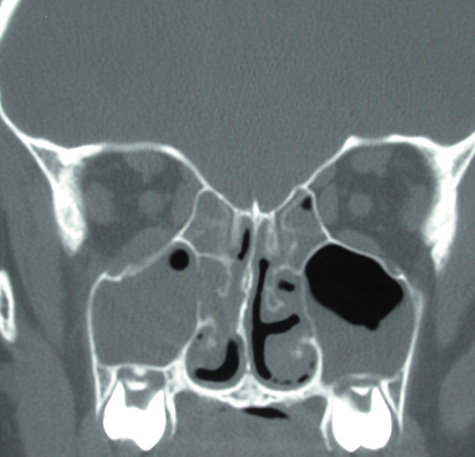

CT shows sinusitis with or without bone destruction and is indistinguishable from other causes of orbital cellulitis.128 MRI may show carotid narrowing, occlusion, and absent flow in the superior ophthalmic vein (Fig. 24).72

Fig. 24. Mucormycosis. A. A 72-year-old patient with acute myelogenous leukemia and invasive fungal sinusitis presented with orbital cellulitis. B. Involvement of hard palate with eschar. C. Fungi in the posterior ciliary artery.